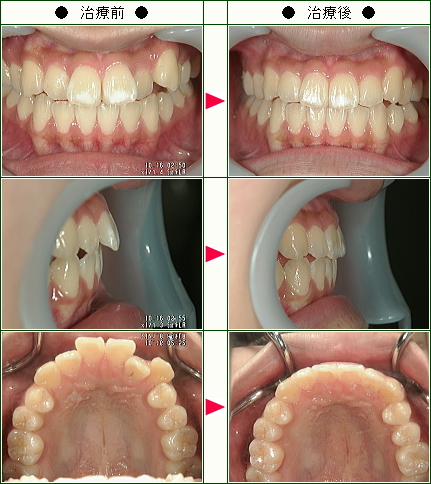

歯のデコボコ矯正の治療症例解説<上だけの症例>(19歳以下)--部分矯正--その4

☆歯のデコボコ矯正症例[N.A様 14歳 女性]

☆歯のデコボコ矯正症例[R.Y様 13歳 女性]

☆歯のデコボコ矯正症例[C.H様 18歳 女性]

☆歯のデコボコ矯正症例[松村様 15歳 女性]

☆歯のデコボコ矯正症例[やはた様 19歳 女性]

☆歯のデコボコ矯正症例[A.W様 15歳 女性]

☆歯のデコボコ矯正症例[O.N様 19歳 女性]

☆歯のデコボコ矯正症例[みき様 16歳 女性]

☆歯のデコボコ矯正症例[小堀様 18歳 女性]

☆歯のデコボコ矯正症例[宗村様 11歳 女性]

-歯のデコボコ矯正の治療解説

-部分矯正, 前歯矯正, 症例写真, デコボコ, 症例